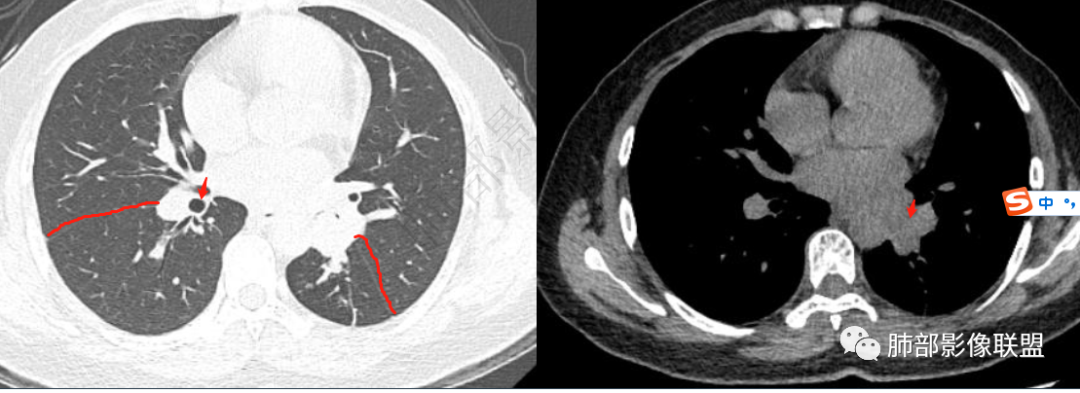

左下肺支气管腔内病灶,有强化,考虑恶性可能。年轻女性,鳞癌罕见;强化后CT值增加20Hu左右,非明显强化,类癌可能性小;远端支气管内有低密度影(粘液栓?),考虑粘液表皮样癌、腺样囊性癌等。鉴别结核

青年女性,间断咳嗽、咯血3年,再发半天,炎性指标、血沉全正常。左下肺近肺门结节,跨叶裂,膨隆分叶,支气管门口截断,平扫密度高,有钙化,增强后强化明显,未见明显坏死及淋巴结肿大,稍远端支气管内低密度影,增强化强化不明显,左下叶后基底段胸膜下结节,内有小空洞,强化明显。思路:一、感染性病变:1、整体一元考虑结核,病史反复三年咳嗽,咯血三年支持,左肺门病灶跨叶伴远端支气管内粘液栓及左下肺胸膜下伴小空洞结节均支持,疑点:前两次发作抗感染治疗均有效好转,本次炎性指标及血沉等均正常不好解释。支气管门口截断不好解释,反复发作三年,无肿大淋巴结不好解释。2、慢性非特异性炎伴机化。病史三年反复,发作时抗感染治疗有效,要考虑。二、肿瘤:1、腺癌,肺门区及胸膜下多中心腺癌,膨隆、分叶,支气管门口截断,强化明显均支持,胸膜下结节强化明显支持,反复发作的症状考虑合并阻塞性炎症。2、类癌,平扫密度较高,有钙化,强化明显支持,3、涎腺类肿瘤,性别年龄要考虑,但增强明显较均匀强化不太支持。4、淋巴瘤,影像表现要考虑,但这个年龄段的淋巴瘤一般为HD,这个不符合。所以可能小。5、极端的二元肿瘤,肺门区类癌,胸膜下腺癌。三、非肿瘤非感染性病变,血管炎,反复发作三年的症状,有过敏性鼻炎,要考虑,需要查血管炎三项和副鼻窦情况排除。临床很简单:下一步EBUS穿刺肺门区及经皮穿刺胸膜下结节。至于读片嘛,还是先考虑恶性(腺癌>类癌>二元癌>淋巴瘤),鉴别诊断:结核>非特异性炎伴机化>血管炎

3年,反复发作,抗炎后好转

左下叶支气管占位才对

远端有病灶,左下叶体积缩小

提示应该是腔内病变堵塞,导致通气不畅,引起远端炎症,抗炎后好转

南边:

平扫密度偏高,60HU,增强后有强化,88HU

这些应该是粘液栓为主

这个病例的关键点在支气管。

我觉得首先应该把支气管重建出来。

我们要看病灶和支气管的关系,腔内的还是腔外突向腔内的,但我看这个是腔内的,附近是不是有淋巴结,这个都需要我们去鉴别。

然后它跟远端病灶的关系,外面病灶引起肺门区病灶,还是肺门区病变导致远端病变。

然后就是前后的变化,三年前或者一年前有什么差异,这个是我们判断的最基本的依据,但是这个缺失,造成方向不明晰,就是猜测,有可能是这种可能,有可能是那种可能。

目前看来看去是腔内的病变引起的,现有的资料不够。